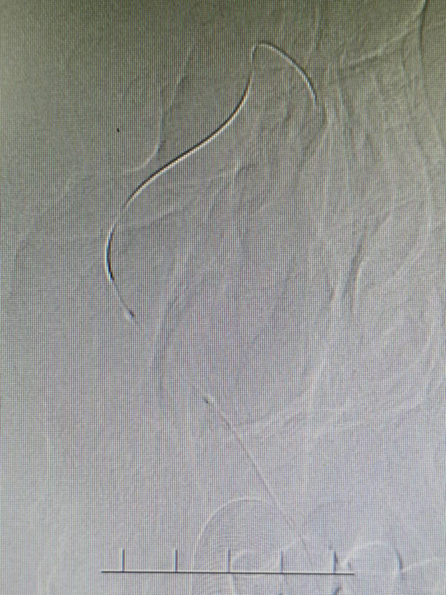

治疗策略:右椎动脉纤细,且左椎动脉开口狭窄40%并斑块形成,内径约1.8mm,与中间导管直径几乎相等,易造成血流阻断,应用6F长鞘在125治疗导管及泥鳅导丝引导下,泥鳅达锁骨下动脉,长鞘置于椎动脉开口下,再送入0.014微导丝及1.5*10mm球囊扩张,选择赛诺神畅 NOVA DES®内药物洗脱支架2.5*12mm植入。

微导丝:0.014in*300mm交换微导丝

1、患者左椎动脉开口狭窄40%,右椎动脉颅内段闭塞,如用中间导管送到左侧椎动脉远端形成有效支撑,但很有可能造成前向血流中断,为此我们用泥鳅导丝置于锁骨下动脉或椎动脉内支撑Guiding在椎动脉开口处,再选用0.014in较硬交换微导丝置入到大脑后动脉P3段,这样就形成了既有前向血流又有效支撑的通路。为置入球囊及支架奠定了良好的基础。如上述方案失败,我们通过交换微导丝送入中间导管,到达狭窄近端再进行球扩加支架的第二方案。